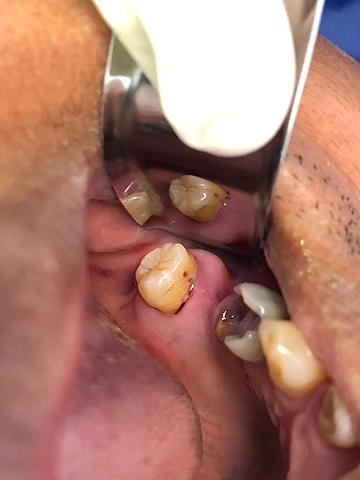

• Preparación para incrustación de las piezas 3.6 y 4.7

Preparación para incrustación de las piezas 3.6 y 4.7

Debido a que la extensión de diente que se tiene que restaurar es amplia se decidió en colocar incrustaciones. Se aísla, y se preparan las paredes de la cavidad de forma convergente. Finalmente se toman modelos y se obtura de forma provisional. El modelo se manda al laboratorio para poder realizar el diseño de la incrustación.